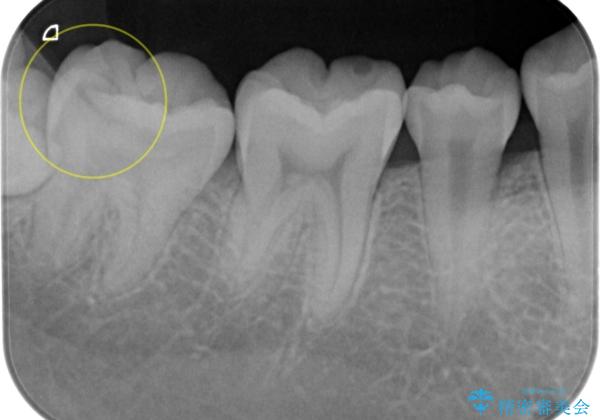

- 検査の結果虫歯が見つかった患者様です。

親知らずを抜歯してから虫歯を除去した後、ゴールドの詰め物で修復します。

比較的大きな虫歯でしたがゴールドでの修復にすることで歯の削る量を抑え、精度の高い治療を行うことができました。

親知らずの問題も同時に解決することで今後の虫歯リスクを抑えています。